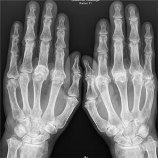

Röntgenfoto om gewrichtsschade door RA te bepalenDe nieuw ontdekte antistof heet anti-CarP (anti-gecarbamyleerd-eiwit). Uit het Leidse onderzoek blijkt dat bij ruim 40% van mensen met RA anti-CarP kan worden gevonden in het bloed.